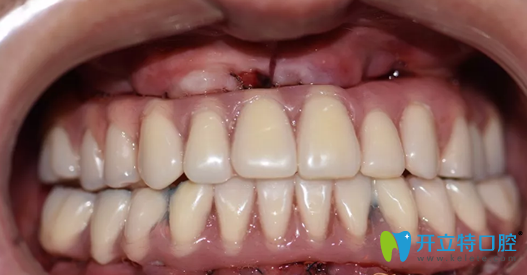

重慶牙博士口腔種植牙術(shù)前照片:

重慶牙博士口腔種植牙術(shù)前照片

這一口牙真的讓人不忍直視,說(shuō)實(shí)話,初看上去真的有點(diǎn)適應(yīng)不良呀,牙周病如此嚴(yán)重,想必莫先生應(yīng)該被牙痛折磨的不清吧。

種植牙術(shù)后即刻照片及修復(fù)后CBCT影像:

重慶牙博士徐孟輝種植牙術(shù)后即刻照片及修復(fù)后CBCT影像

種植完即刻牙齒情況照片:

徐孟輝種植完即刻牙齒情況照片

哇塞,這樣的牙齒是不是看上去順眼了很多,如果沒(méi)有人說(shuō)的話,你能看出莫先生的牙是后天種植上去的嗎?